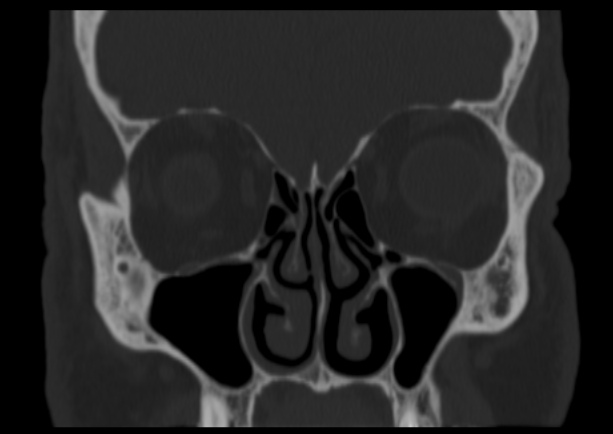

Rhinology

- Functional open and closed septorhinoplasty (excludes cosmetic work)

- Septoplasty

- Endoscopic turbinectomy

- Functional endoscopic sinus surgery (FESS)

- Anterior skull base surgery for frontal sinus drainage, CSF leaks etc.

- Management of Allergic Rhinitis, Acute Sinusitis and Chronic Rhinosinusitis

- Endoscopic Dacrocystorhinostomy (Tear Duct Surgery)